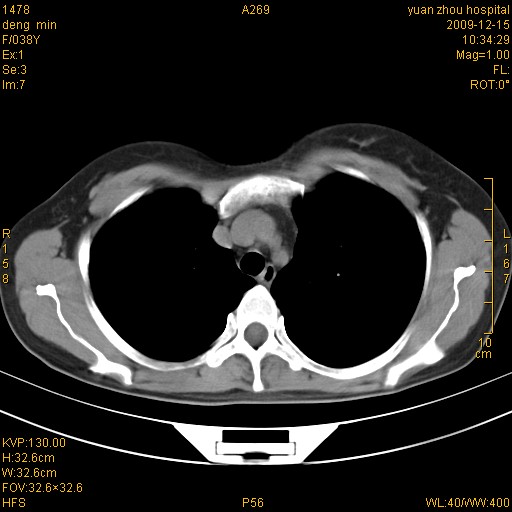

标题: CT23919:F38Y 咳嗽月余 [打印本页]

标题: CT23919:F38Y 咳嗽月余

右肺中下叶、左肺上叶舌段及左肺下叶支气管扩张合并感染。